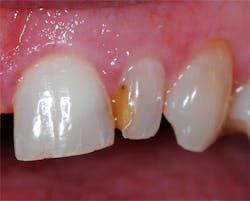

A local anesthetic (4% Septocaine with 1:100,000 epi, Septodont) was administered. The defective composite was removed with a 330 carbide bur (SS White) in a high-speed handpiece with water. Recurrent decay was noted at the gingival margin and was removed to reveal sound, intact dentin. An old cavity liner had been placed under the defective composite, and a small portion of this was left intact over the center of the preparation. The cavity liner was intact and not displaceable with an explorer (figure 2). To minimize postoperative sensitivity, a selective-etch technique was used. A 37% etching gel was applied to the enamel areas of the tooth for 20 seconds, then rinsed and dried. Cotton roll isolation was placed.

Figure 2: The old composite was removed with a carbide bur, and the enamel margins were roughened with a diamond bur in a high-speed handpiece.